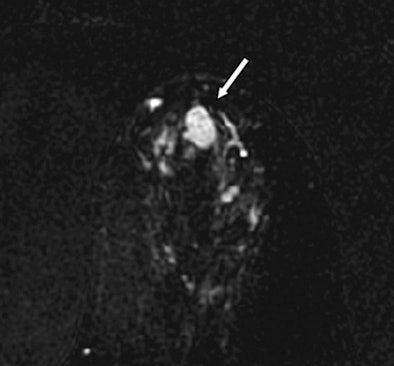

| Images are of a 61-year-old woman with a history of right-breast ductal carcinoma in situ. Axial dynamic contrast-enhanced MRI image (above) shows 13-mm lobular heterogeneously enhancing mass (arrow) in the subareolar region of the left breast. All images courtesy of Radiology. |

![]() |

| The lesion (arrow) is hyperintense on axial DWI (above) and has a low ADC on an ADC map (below). No evidence of carcinoma was detected at excisional biopsy. |